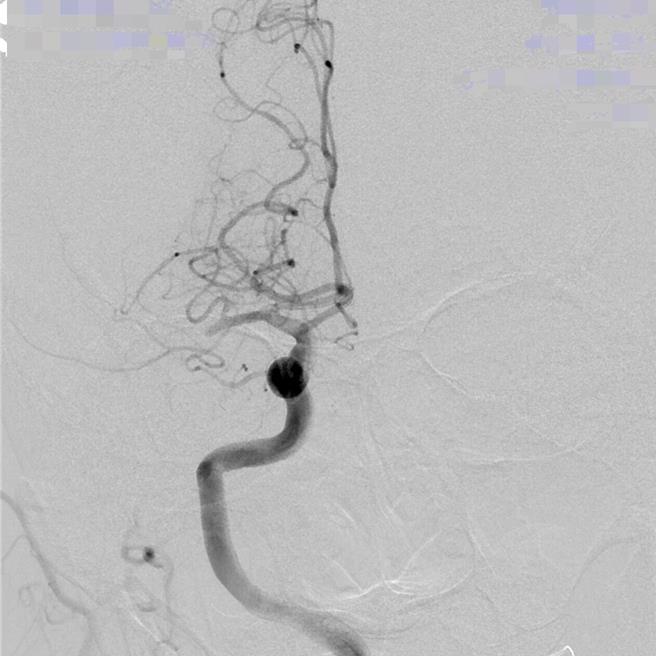

进行颅内动脉取栓治疗后,将血栓取出清除,恢復血流。(光田医院提供)

神经放射治疗科副院长严宝胜指出,治疗时进行动脉取栓评估,会用医疗AI智慧仪器设备去侦测哪一条血管堵住,仪器会侦测出血栓确切位置,再使用器械进入血管内把血栓取出。从该病患血管摄影可看出,右半边后面的血管都不见了,也就是血栓塞住血流过不去,影响的范围很大,必须尽快进行颅内动脉取栓。